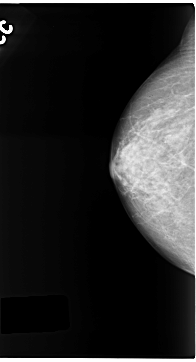

C_0141_1.RIGHT_MLO

RIGHT_CC LINES 4704 PIXELS_PER_LINE 2544 BITS_PER_PIXEL 12 RESOLUTION 50 NON_OVERLAY